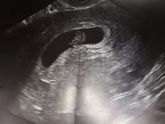

Девочки все таки не выдержала я до 15 числа . Мысли глупые в голову лезут и грудь болеть что то перестала и не мутит больше . Вот сегодня поеду на узи что бы посмотреть малыша и сердечко послушать . А 15 пойду на учет вставать . Молюсь что бы все было … Читать далее

Сегодня записалась на узи на 15 декабря, хочу что бы уже наверняка и сердцебиение прослушивалось и маленького хорошо было видно. На учет буду вставать в частную клинику так как у нас в городе только перинатальный центр и народу там немеренно. Сноха во … Читать далее